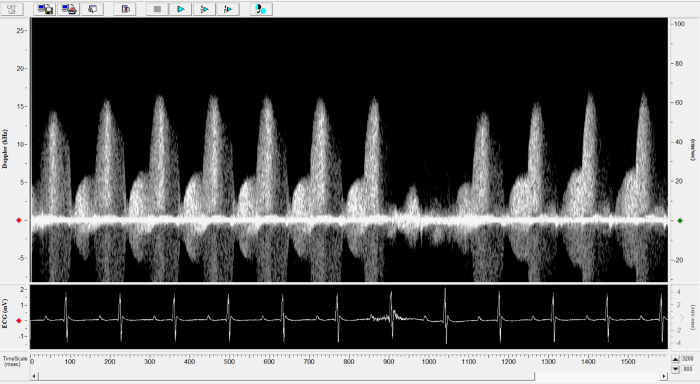

Imaging gallery - Doppler Flow Velocity System

Mouse - Mitral Inflow. Image Credit: Scintica Instrumentation Inc.